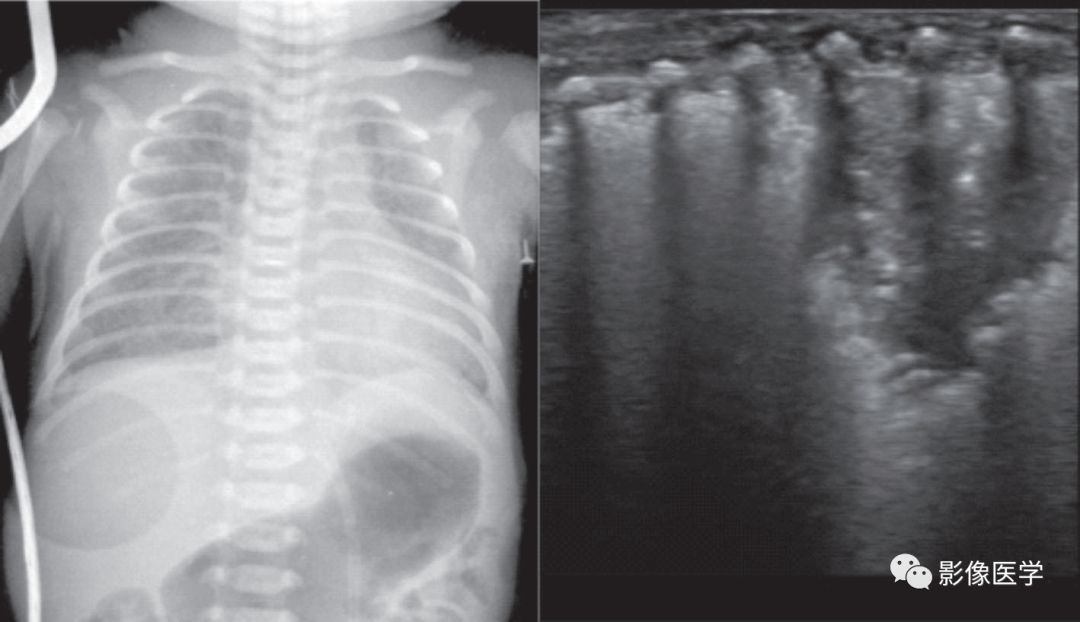

图6-3 重症感染性肺炎(2)

胎龄32+6周,出生体重2 400g。出生后7d,呼吸困难,胸部X线检查结果符合新生儿肺炎改变。肺脏超声显示双肺大面积肺实变伴支气管充气征,实变区边缘不规则,胸膜线模糊或消失,A线消失。